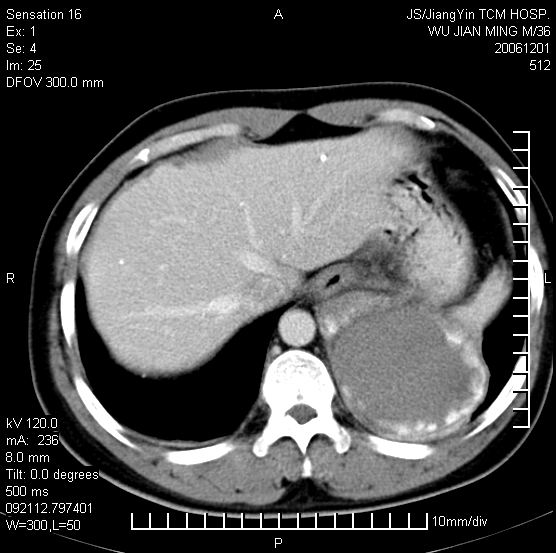

以下是引用dyqct在2006-12-1 21:17:00的发言:[br]左心缘旁及后肋膈窦区见巨大椭圆形混杂密度肿块,周围见大小不等斑片状钙化,内部无强化,周围包膜轻度强化,心脏明显受压变形,即明显占位效应,肿块广基与心包、膈相连。肝、脾内、肝门见多数小结节状钙化影。[br]考虑:1、左心缘旁及后肋膈窦区慢性包裹性胸膜炎(结核性);[br] 2、肝、脾及肝门淋巴结核已钙化。[br]

以下是引用zyx168在2006-12-2 10:10:00的发言:[br][br]肝脾肺内多发钙化灶